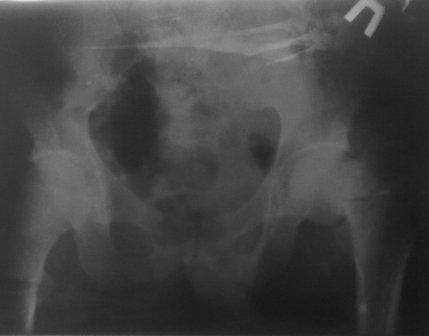

Как предлагали уважаемые коллеги, сегодня наложили спице-стержневой дистрактор таз-бедро, перед этим попробовали закрытую остеоклазию под в/в анестезией, движение в т/б суставе ( или в ложном суставе! ) восстановлен.

Р-снимки сразу п/о, следующий после дистракции, аксиальная - прощу извинения за плохое качество снимков.

Мне кажется надо еще продолжать постепенную дистракцию. И еще которая наверху шейки по моему это осколок от шейки, и она фиксирована оссификатом надвертлужной обл. Поэтому при повторной операции видимо придется открыто мобилизовать т/б сустав.

С уважением Абдурашид.